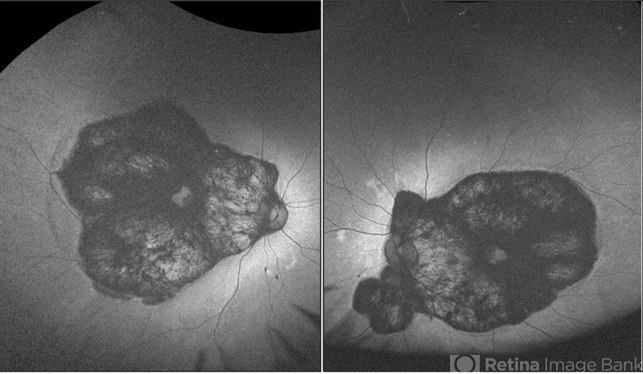

- central areolar choroidal dystrophy (CACD), autofluorescence imaging

- 54 year old female well circumscribed, bilateral and symmetrical lesion with loss of retinal and choroidal tissue in the macular area.